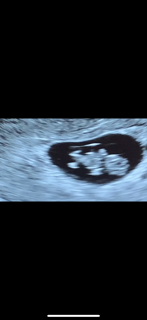

写真:8w5d:ぺいきさん

2週間前はまだサイズも小さく心拍も確認出来ず不安でしたが今回心拍確認とちゃんと成長してて安心しました!

次回2週間後なのでそれまで楽しみに穏やかに過ごせたらと思います\(^o^)/